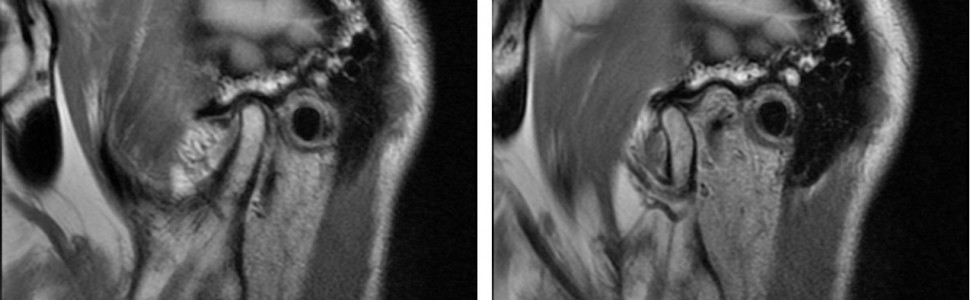

Dysfunkcje stawów skroniowo-żuchwowych są często występującą grupą zaburzeń dotyczących układu stomatognatycznego. Ich objawy mogą być różnorodne, od bezbólowego zaburzenia toru prowadzenia żuchwy do trzasków i trzeszczeń podczas odwodzenia żuchwy, którym towarzyszą samoistne lub sprowokowane żuciem objawy bólowe w okolicy przedusznej. Współczesne metody obrazowania struktur wchodzących w skład stawów skroniowo-żuchwowych pozwalają na wczesne wykrycie zmian morfologicznych, a co za tym idzie – wczesne podjęcie leczenia i prognozowanie postępu zmian. Celem pracy jest porównanie dwóch metod obrazowania poszczególnych elementów stawów skroniowo-żuchwowych: stożkowej tomografii komputerowej (CBCT) i obrazowania metodą rezonansu magnetycznego (MRI).

The temporomandibular joint (TMJ) dysfunctions represent a frequent group of disorders occurring in the stomatognathic system. Their symptoms may range from painless abnormalities of the mandibular path to snapping and crackling during mandibular abduction, which may be accompanied by either spontaneous or chewing pain in the pre-parotid region. Modern methods of imaging the structures that make up the temporomandibular joint allow early detection of morphological changes, enabling early treatment and prognosis of growth changes. The aim of this study is to compare two methods of imaging individual elements of the temporomandibular joint: cone-beam computed tomography (CBCT) and magnetic resonance imaging (MRI).